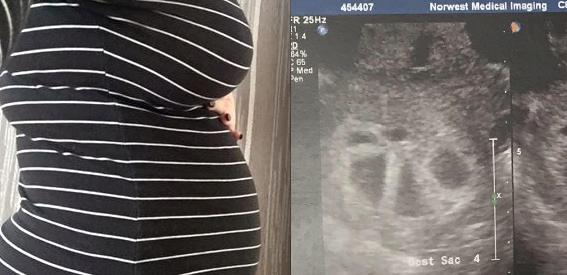

她產檢時才發現懷的不止一個,「寶寶數量」多到數不清,連醫生都嚇傻了!沒想到「超音波」竟照到了...

▼這名澳洲的媽媽叫做Kimberly Tucci,她已經是兩個孩子的媽了,但她很快就...